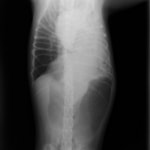

■ 症例:10歳 ドーベルマン 主訴:突然の嘔吐、虚脱

術前のレントゲン

身体検査上、鼓腸を伴う腹囲膨満、口腔粘膜の蒼白などが認められます。確定するには、レントゲン検査の実施が重要となります。その際、著しく拡張した胃が確認され、特徴的な捻転ラインが認められます。